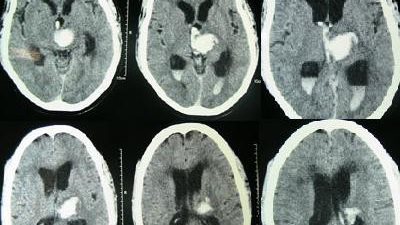

لأول مرة في مستشفيات الدقهلية.. عمل قسطرة علاجية لسحب جلطة بالمخ لسيدة تبلغ من العمر 70 عامًا

شقيق مصاب بنزيف في المخ يستغيث لطلب قسطرة علاجية على المخ